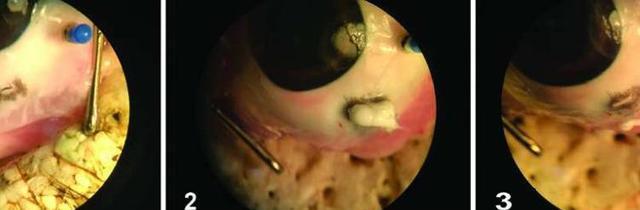

令人欣喜的是,由南加州大學(xué)(USC)的科學(xué)家和工程師組成的多學(xué)科團(tuán)隊(duì)很快就能解決這個(gè)問題。他們開發(fā)了一種可逆的、熱敏性的臨時(shí)密封膠。當(dāng)應(yīng)用于眼睛時(shí),該密封膠會(huì)從液體轉(zhuǎn)變?yōu)槌瑥?qiáng)的半固體以封住創(chuàng)口。當(dāng)病人準(zhǔn)備好接受手術(shù)時(shí),醫(yī)生可以通過添加冷水來移除密封膠。該研究結(jié)果發(fā)表在12月6日的《科學(xué)轉(zhuǎn)化醫(yī)學(xué)》雜志上。

該研究團(tuán)隊(duì)正研究一種被稱為聚N-異丙基丙烯酰胺(PNIPAM)的水凝膠視網(wǎng)膜植入物材料。它有一個(gè)獨(dú)特的屬性,并因此十分適合被用于治療眼損傷:當(dāng)冷卻時(shí),水凝膠變成了一種易于涂抹的液體;而加熱后,它則會(huì)變成粘性強(qiáng)的半固體,應(yīng)用時(shí)所需要的只是一些簡(jiǎn)單的縫合。

“最初的水凝膠轉(zhuǎn)變溫度非常接近人眼的溫度,但為了確保士兵或醫(yī)生一將其涂在眼睛上時(shí)就能形成牢固的密封膠,我們必須改變它的屬性。”論文的第一作者,南加州大學(xué)維特比學(xué)院化學(xué)工程與材料科學(xué)系的博士研究生候選人Niki Bayat說:“考慮到它完美且可逆的密封性,智能水凝膠有望成為下一代組織粘合劑。”

當(dāng)醫(yī)生準(zhǔn)備手術(shù)時(shí),水凝膠可以通過冷卻水轉(zhuǎn)化到低粘狀態(tài)。

為了確定這種材料的功效,研究人員用一只兔子作為模型。結(jié)果表明,將水凝膠涂抹于穿透性眼部損傷時(shí),水凝膠可舒緩眼內(nèi)的壓力,這可能是防止視網(wǎng)膜脫離并最終導(dǎo)致視力喪失的關(guān)鍵。此外,在長(zhǎng)達(dá)四周的使用中也沒有炎癥或感染的癥狀。研究人員希望在2019年開始對(duì)人類進(jìn)行臨床安全性測(cè)試。